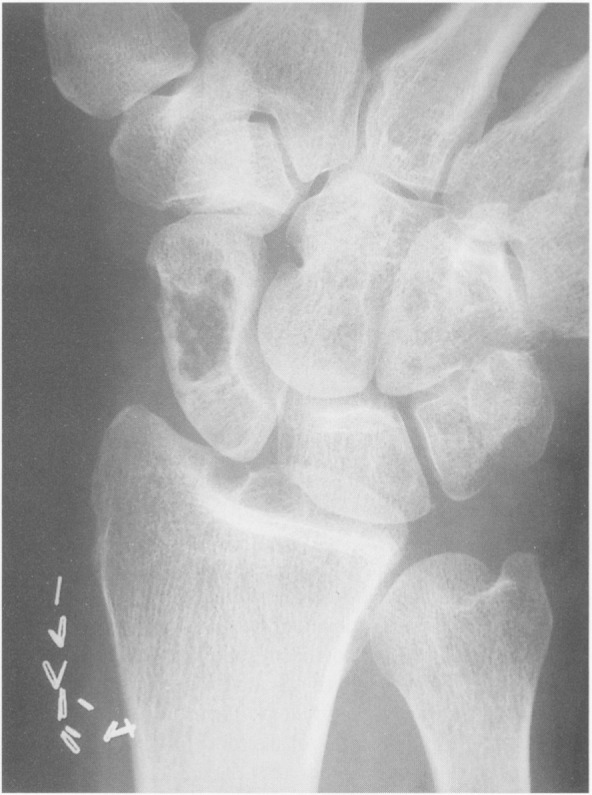

Рентгенография скелета: характерно выявление кист в головках бедренных костей, плечевых костях, надколенниках, вертлужных впадинах и позвоночнике[6].